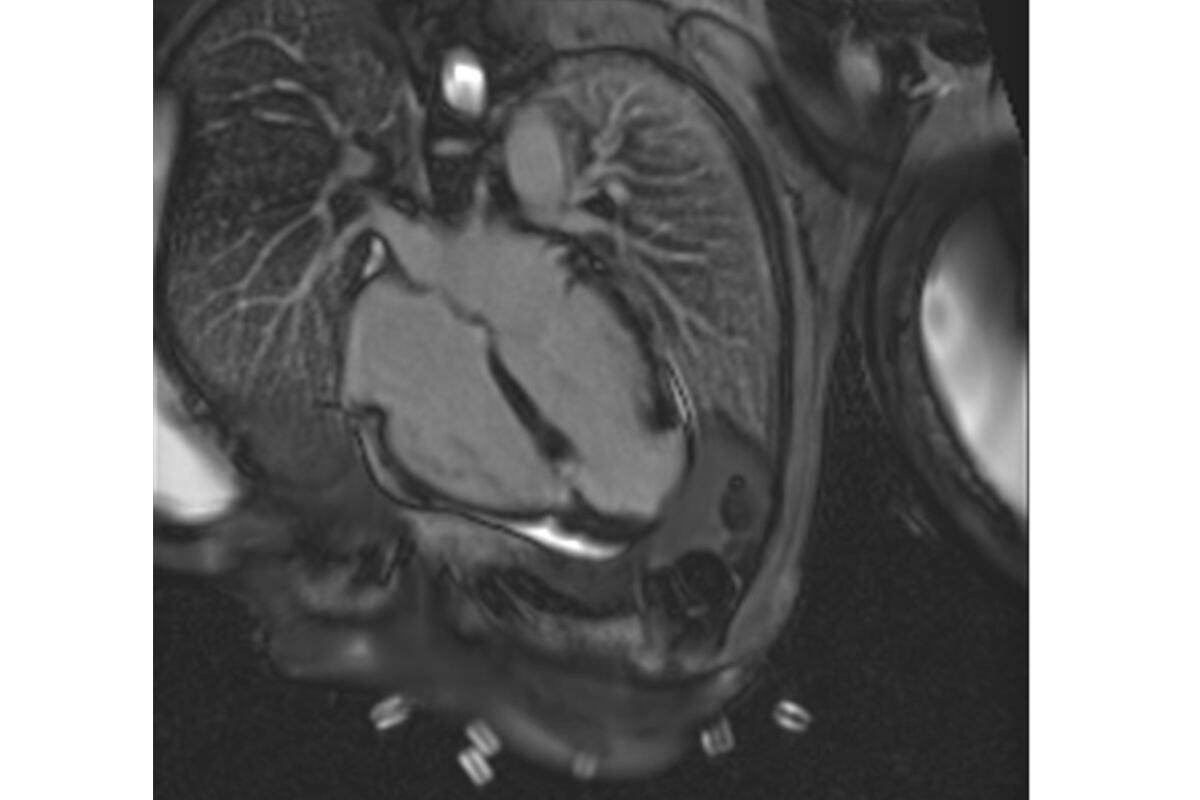

L’intelligenza artificiale, o AI, toglierà il lavoro ai tecnici di radiologia per le risonanze magnetiche? «Niente di tutto questo – rassicura il professor Marco Salvatore Nobile dell’Università Ca’ Foscari di Venezia – grazie al software che abbiamo sviluppato supporteremo i tecnici nella scelta di un parametro di scansione, il cosiddetto “tempo di inversione”, necessario per l’ottimale visualizzazione del tessuto cicatriziale nel cuore durante le risonanze magnetiche cardiache. In questo modo, toglieremo stress e fatica al tecnico che è già impegnato in un esame lungo e complesso, facilitando il processo per migliorare la qualità delle diagnosi».

Ma cosa fa nello specifico questo applicativo? «Pensiamo al talento di un fotografo nell’individuare il momento giusto per lo scatto perfetto – spiega Nobile – fino adesso gli operatori sanitari hanno dovuto sviluppare una capacità simile, che mette insieme la conoscenza tecnica con l’esperienza e le caratteristiche peculiari di ogni paziente, per poter “mettere a fuoco” il cuore dopo la somministrazione di mezzo di contrasto, in modo da evidenziare eventuali “danni” al muscolo cardiaco. La scelta dell’attimo migliore per lo “scatto” perfetto corrisponde al “tempo di inversione”. Tutto questo permette di avere la migliore rappresentazione della situazione e di formulare una diagnosi il più esatta possibile».

«L’uso dell’intelligenza artificiale permette di affinare al massimo la scelta del momento in cui eseguire lo “scatto” – continua – perché con la sua potenza di calcolo, e avendo appreso un grande numero di informazioni estratte da risonanze cardiache di ottima qualità eseguite in passato, THAITI è in grado di comunicare all’operatore il momento ideale in cui attivare il processo di acquisizione dell’immagine, visto che il buon esito è legato alla quantità di liquido di contrasto presente nel cuore e il tempo di inversione è differente per ogni paziente e varia ripetutamente nel corso di uno stesso esame».